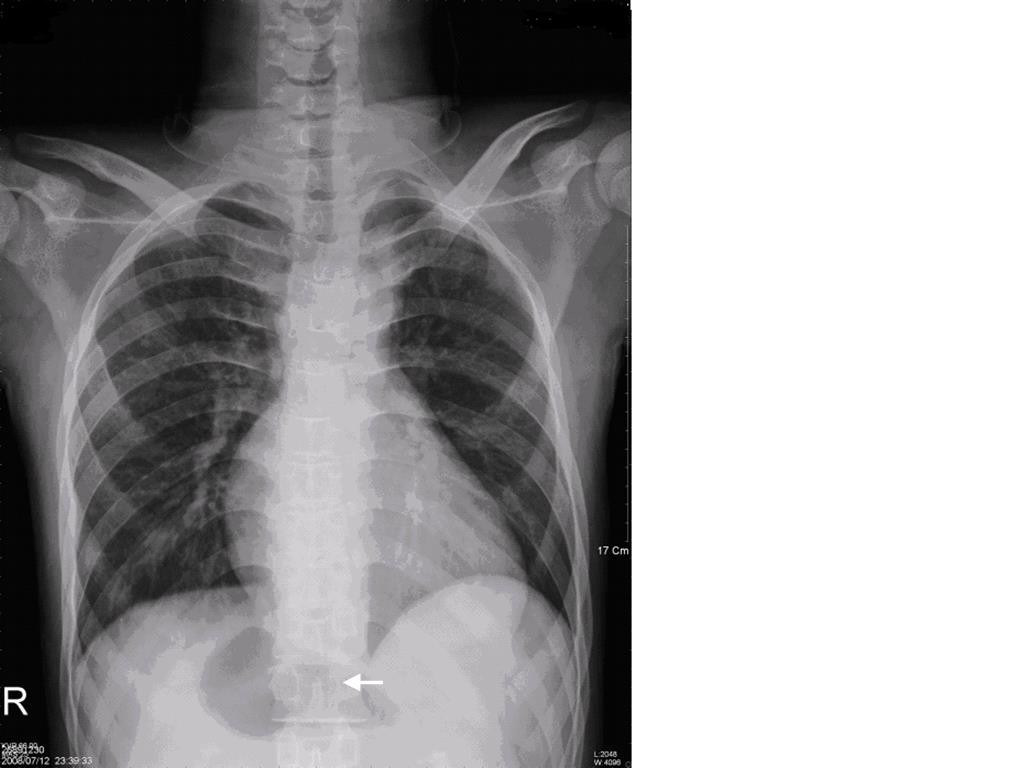

A twenty years old male, was admitted through Emergency Room (ER) at 10:30 pm due to traffic accident. The Glasgow Coma scale at the ER was E4V5M6, and the vital signs were stable with blood pressure of 141/82 mmHg, tachycardia at 111 beats/min, respiratory rate at 19/min, and body temperature at 36.5℃. His arterial saturation when arriving in the ER was not disclosed in the chart. Past history of cardiac surgery (diagnosis: unknown) at the age of five was told by the patient and there was no limitation on physical activity thereafter. Physical examination revealed head injury with ecchymosis over left eye with symmetric pupil size. Laboratory data revealed hemoglobin (Hb) 17.2 gm/dl; hematocrit (Hct) 55.7%, mean corpuscle volume (MCV) 69.1 fl; Sodium 133.3 mEq/L, Potassium 3.07 mEq/L, BUN 7 mg/dL, Creatinine 0.8 mg/dL, GOT 125 IU/L, and GPT 59 IU/L. Electrocardiogram showed sinus tachycardia and roentgen findings demonstrated no fracture of rib cage or spine except right femoral shaft fracture and centrally located gastric bubble (Figure 1). Brain CT revealed no intracranial hemorrhage, but fractures in left maxillary sinus and left lateral orbital wall. Abdomen CT was negative for internal bleeding, but centrally located stomach was noted (Figure 2A, B). After consultation by orthopedic surgeon, patient was scheduled for open reduction and internal fixation for his right femoral shaft fracture.

Figure 1. Plain chest film disclosed extraordinary cardiac shadow and centrally-located gastric bubble (white arrow)

The cardiac anomalies in cases with asplenia tend to be more severe than in polysplenia. Asplenia is frequently accompanied with functional univentricular hearts, complete atrioventricular canal defects, anomalous pulmonary venous drainage, obstruction to pulmonary outflow, bilateral superior vena cava, and interruption of the inferior vena cava [10]. All the above anomalies could be found in our patient (Table 1 & Figure 1). In addition, there are extracardiac anomalities, including intestinal malrotation, midline liver, trilobulated left lung, asplenia; rarely, fused adrenal glands, hypoplastic or horseshoe kidney, and anal atresia [11]. Morphologic anomalies of peripheral red blood cells, such as HJ bodies, are evidence of a nonfunctional spleen which failed in filtrating abnormal erythrocytes, such as HJ bodies, from the circulation.

Pre-anesthetic evaluation for emergency surgery is often under tight time constrain which might lead to overlook of laboratory data or patient’s conditions. In this case, the decision to postpone surgery to observe for DICH had prevented us from giving anesthesia to a patient with Ivemark syndrome. In fact, an opportunity to review the patient’s medical history and performing more thorough physical examination would facilitate early diagnosis of patient’s underlying condition. Cyanotic lips, clubbing fingers, precordial scars of previous open-heart surgery, and heart murmurs, secondary polycythemia with microcytic cells on the hemogram, extraordinary cardiac shadow and centrally located gastric bubble on the plain chest film (Figure. 1) were all indications of a congenital heart disease complicated with chronic hypoxemia. Total occlusion of B-T shunt may happen during stressful condition leading to reduced or near no flow entering the pulmonary circulation. In such conditions, extracorporeal circulation (ECC) will be very essential. Therefore, transfer of patient to hospitals equipped with ECC support should be considered once the patient’s condition is being stabilized.